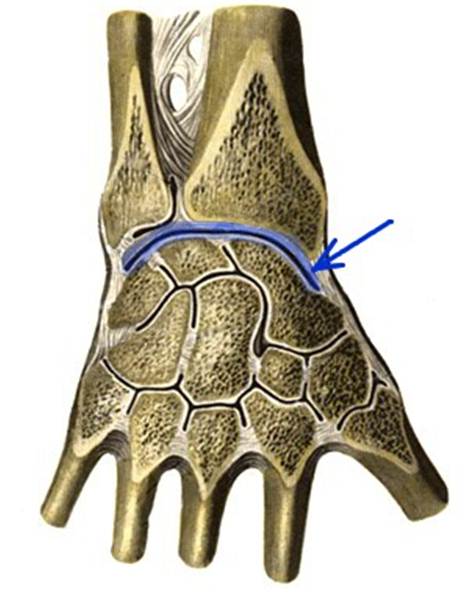

S: Стрелка указывает на art. Radiocarpalis

S: Стрелка указывает на art. Mediocarpalis

S: Стрелка указывает на art. Carpometacarpalis

S: Стрелка указывает на art. capri

S: Стрелка указывает на discus articularis